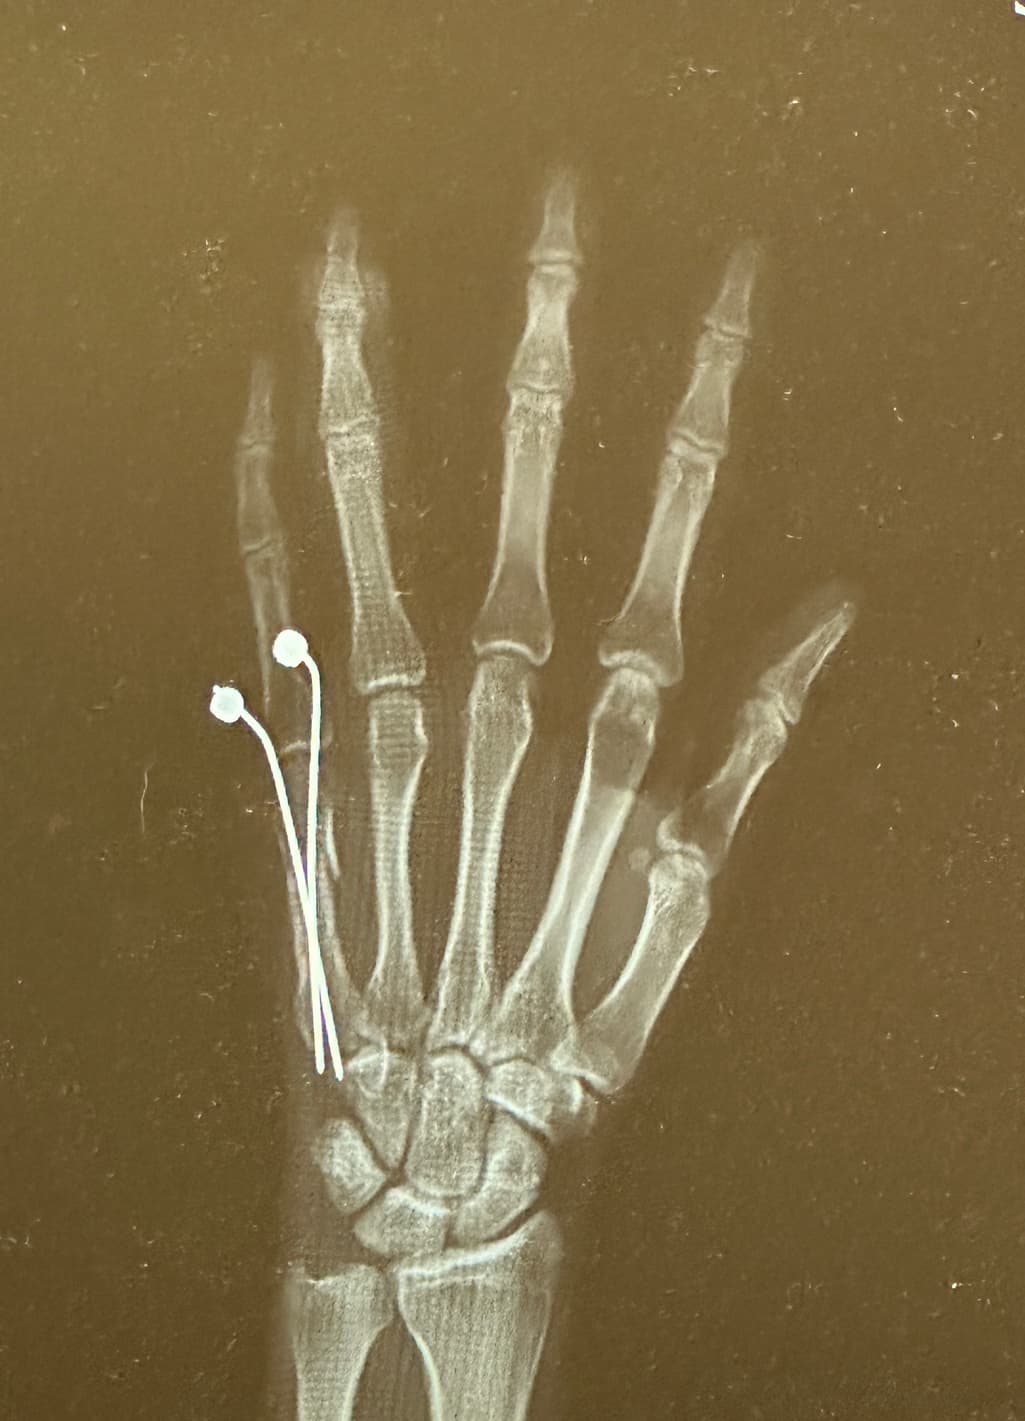

중수골 골절 핀수술 21일차 잘 붙고있는건가요 ?

제목처럼 중수골 골절 고정핀 수술 받은지 21일차 입니다 ! 골진이 차는 느낌도 나고 통증도 아예 사라져서 병원에 방문하여 사진촬영해봤는데 드레싱하구 딱히 모 말씀이 없으셔서 지금 잘 낫고 있나 궁금하여 질문드립니다.

중수골 골절 후 21일이 지나 통증이 사라지고 골진이 차는 느낌이 있다면 회복이 잘 진행되고 있는 것으로 보입니다 병원에서 특별한 문제 없이 드레싱을 해주셨다면 긍정적인 신호입니다.